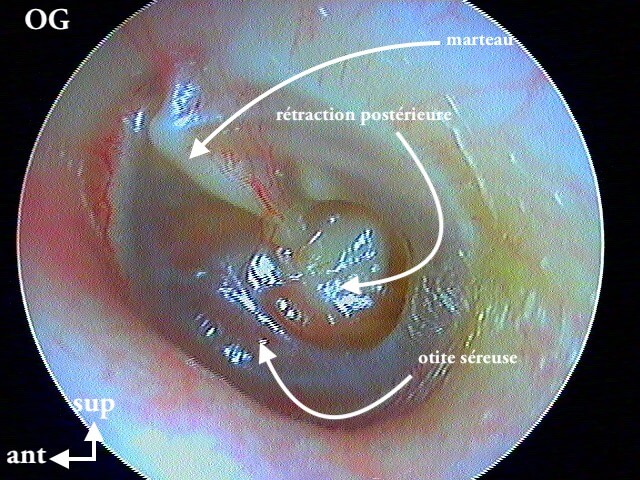

8 POCHE DE RÉTRACTION (ou ATÉLÉCTASIE)

C'est volontiers dans mon expérience la pathologie la plus importante et la plus difficile du diagnostic otoscopique pur. On bascule entre la surveillance clinique annuelle (abstention thérapeutique) et l'interventionnisme chirurgical pour éviter le cholestéatome (qui parfois est iatrogène pour l'audition résiduelle).

J'utilise plus le terme de poche de rétraction plutôt qu'otite atéléctasique.

Donc il faut caractériser ces poches de rétraction (+/- associée à myringosclérose, perforation tympanique, OSM) par:

1/autonettoyante: non cholestéatome

2/ mobilisable au Valsalva: pas d'aérateur (juste surveillance annuelle)

3/ contrôlable à l ’optique: pas de tympanoplastie (DANGER si on ne voit pas le bout de la poche qui s'invagine: risque de cholestéatome)

4/ localisation: pars flaccida (rétraction atticale ou épitympanique) ou pars tensa (rétraction atriale ou mésotympanique)

On peut aussi les classer en:

- non dangereuses : non marginales (n'atteignant pas le sulcus osseux), autonettoyantes (épiderme normal) et décollables (n'oubliez pas mon 2ème conseil en introduction...) ;

- dangereuses: marginales, dyskératosiques (desquamantes: accumulation de squames), fixées au plan osseux sous-jacent (osselet ou articulation incudo-stapédienne ou caisse).